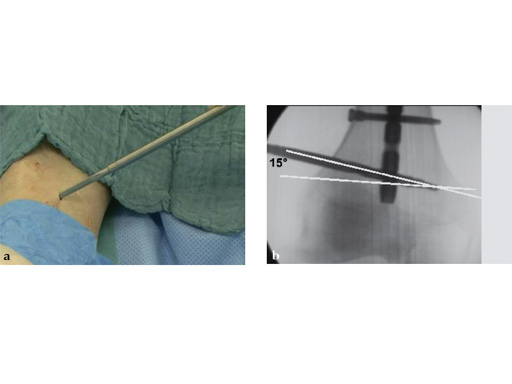

Drilling does not have to be very precise as the ASLS tolerates deviance. An exact amount cannot be given but up to 15 seems to be unproblematic (Fig 4).